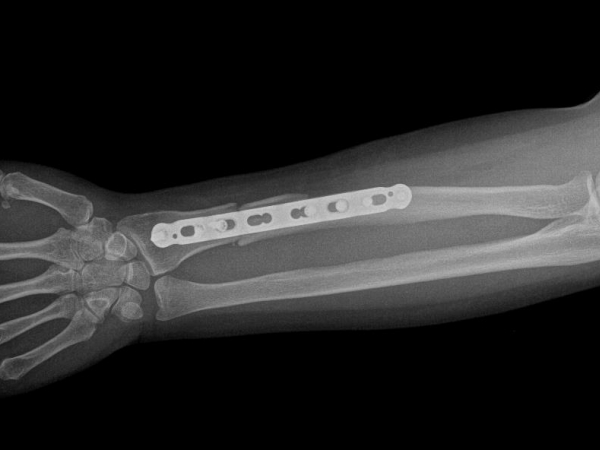

TRUE LOCK 3.5mm Ulna Radius Plate

TRUE LOCK 3.5mm Ulna Radius Plates are indicated for fractures of ulna, radius and fibula shaft.

Radius and ulna body fractures differ from other diaphyseal fractures due to the relationship between both bones and the fractures can affect the elbow and wrist joints. In adulthood, forearm fractures often require surgical treatment, as they are noticeably displaced and unstable.

Images Gallery